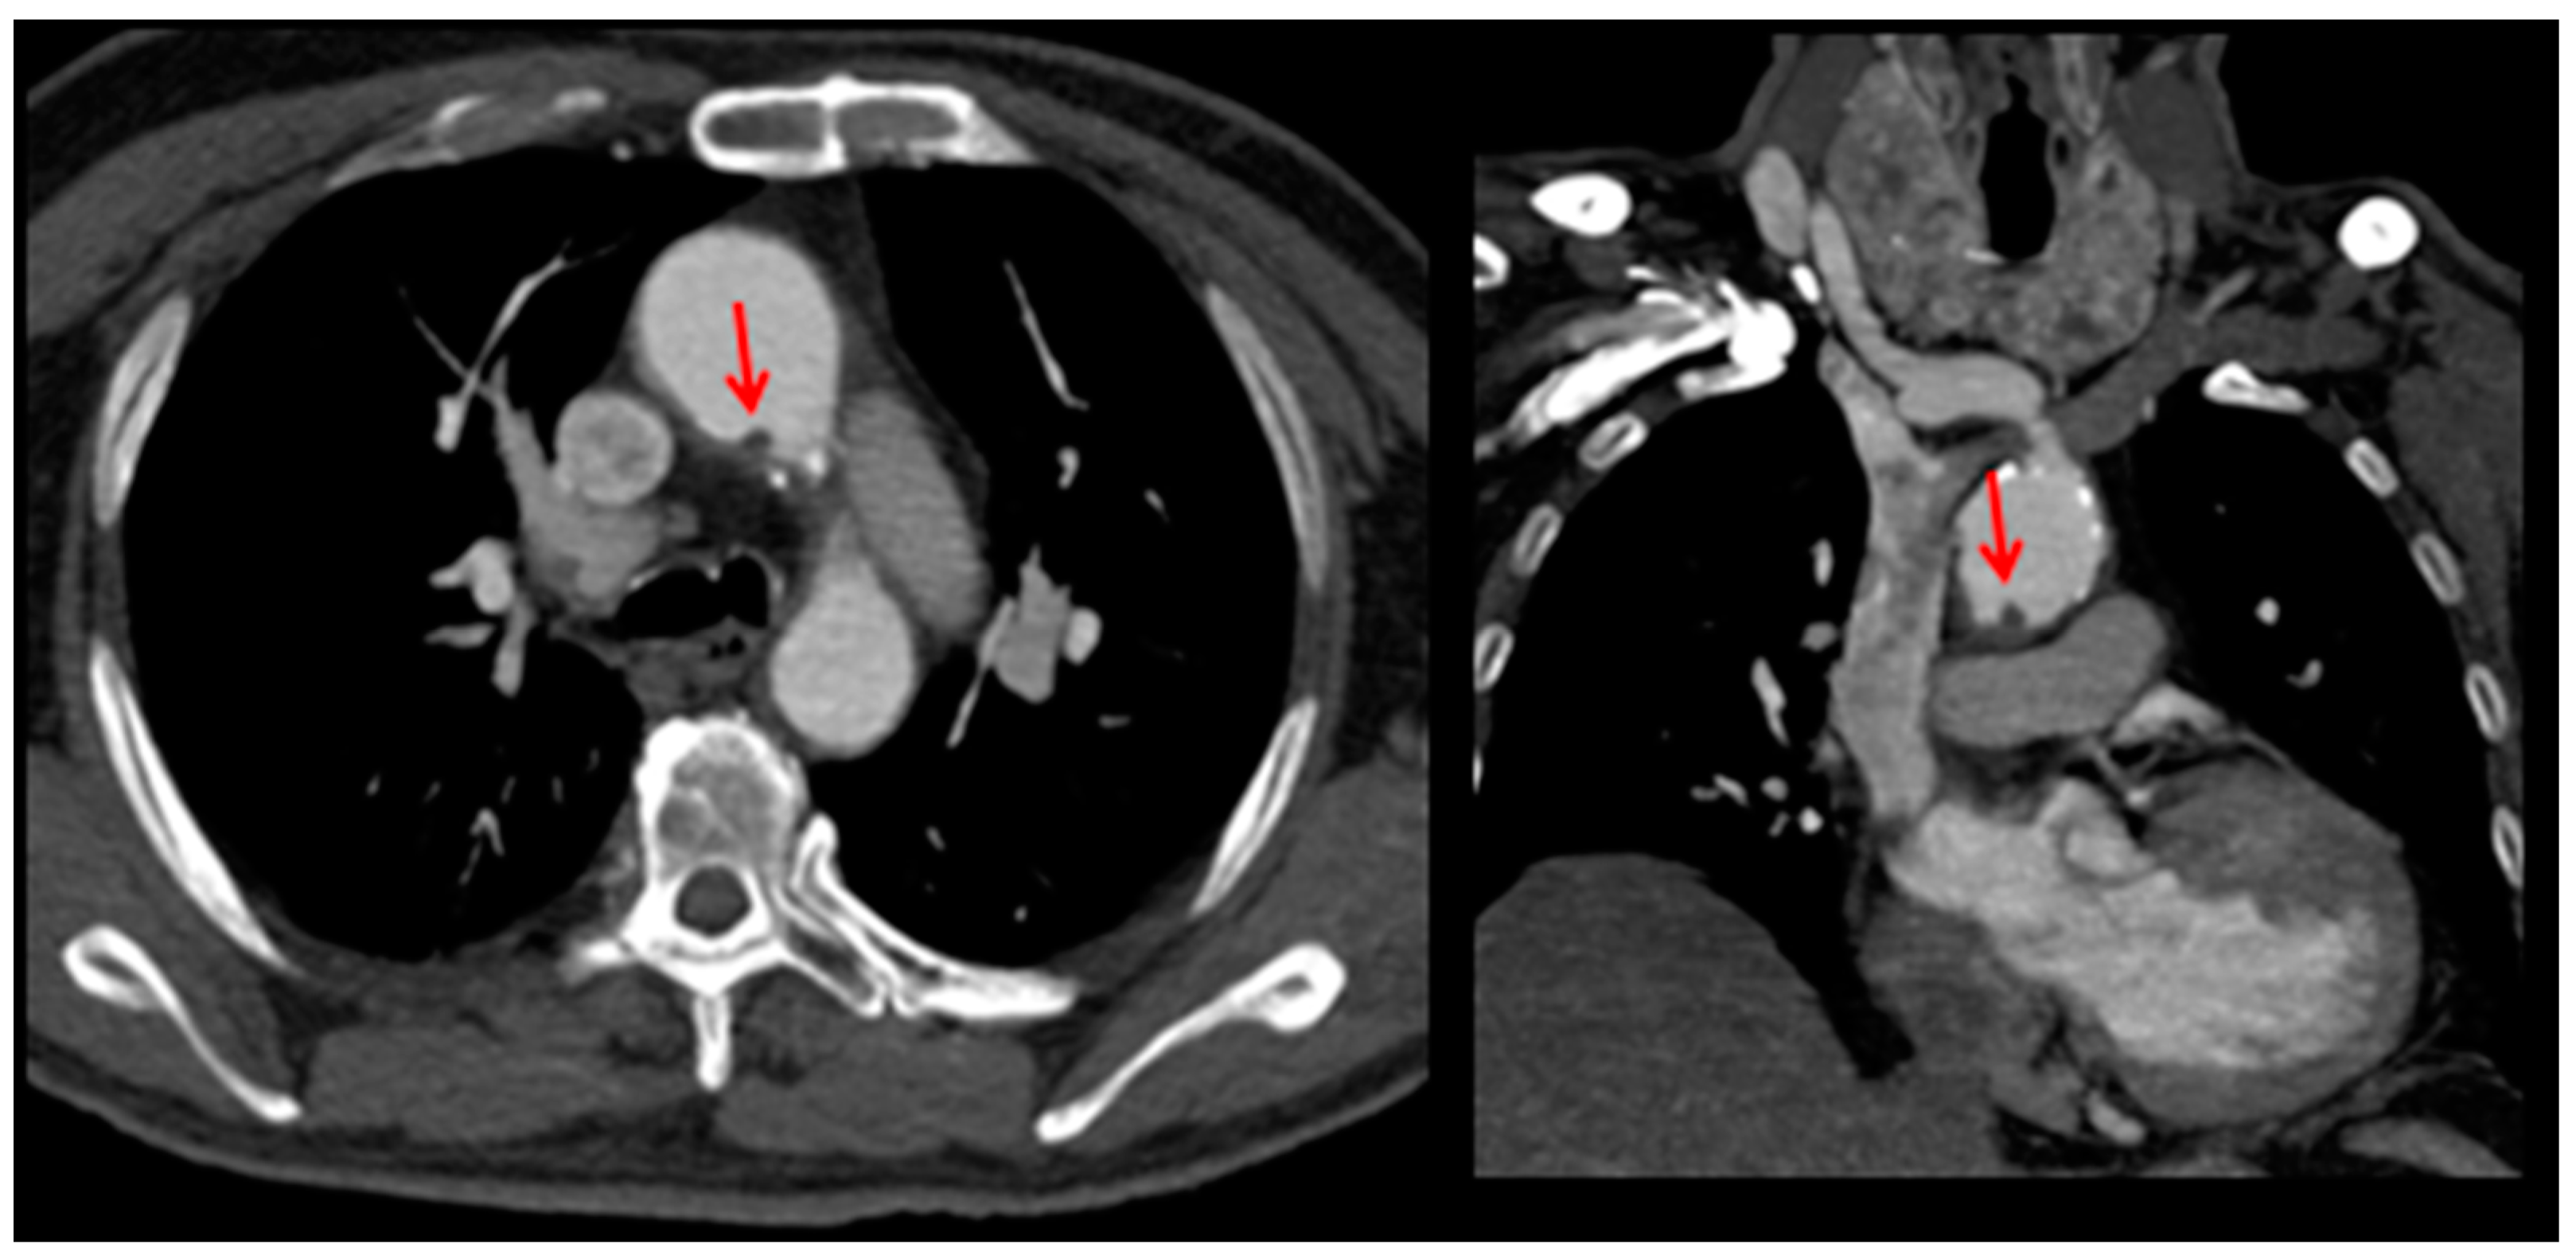

2. Case Presentation